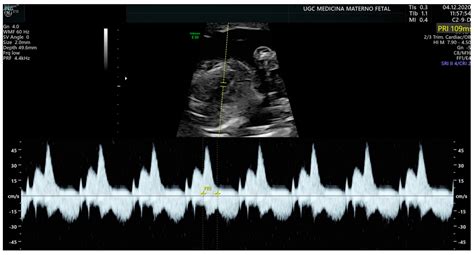

The Normal PR Interval Range typically falls between 120 to 200 milliseconds (ms). This range is considered normal because it indicates that the electrical impulse is traveling through the heart’s conduction system at an appropriate speed. Deviations from this range can indicate various cardiac conditions, such as heart block or other conduction abnormalities.